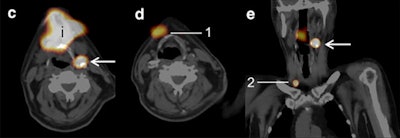

All patients underwent sentinel lymph node biopsies through a two-day protocol that included injections of technetium-labeled nanocolloidal albumin (Nanocoll, GE Healthcare) at the closest proximity of the primary tumor. Planar lymphoscintigraphy was started directly after injection of the tracer. Planar and SPECT images were acquired with a SPECT/CT gamma camera (Siemens Healthineers). The addition of SPECT/CT to planar images was retrospectively analyzed for the number of additional sentinel lymph nodes, for more precise localization of sentinel lymph nodes.

A nuclear physician, head and neck surgeon, and an investigator with considerable experience in sentinel lymph node biopsies and early-stage oral cancer then evaluated the images. The group first read the planar lymphoscintigraphic images alone, then compared the planar results with the SPECT/CT to determine additional information gleaned from the hybrid modality.

SPECT/CT detected 15 additional sentinel lymph nodes in 14 patients (22%). The new discoveries were related to other sentinel lymph nodes that had been found in the same, adjacent, and nonadjacent levels or on the other side of the neck. In two (14%) of these patients, positive sentinel lymph node identification was due to the addition of SPECT/CT. In addition, metastases were found in two sentinel lymph nodes (13%).

SPECT/CT also was instrumental in discerning masses among the 66 patients. In five cases (8%) in which planar lymphoscintigrams leaned toward diagnoses of sentinel lymph nodes, SPECT/CT reversed the finding to nonsentinel lymph nodes. Also, there were four false-negative sentinel lymph node biopsy procedures in this cohort.

"Due to the better topographical orientation, the anatomical levels of the sentinel lymph nodes had been changed in 28% of the patients and better delineation against surrounding tissues could be done," the authors noted.